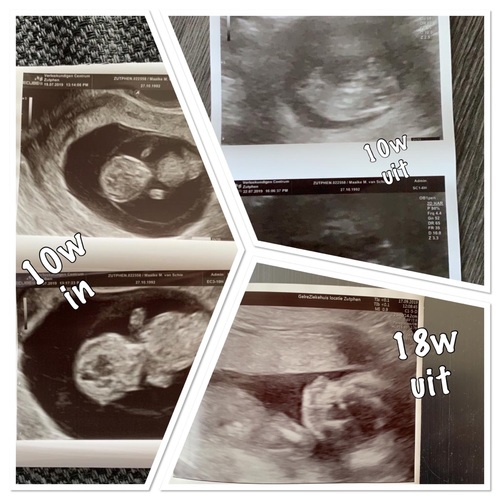

Hoi hier een uit en inwendige echo gehad. Ik was 10 weken toen ze de eerste echo maakte wij wisten niet hoe ver ik was en was dus al 10 weken de eerste keer dus inwendig. Mochten 2 dagen later terug komen omdat kindje niet wilde draaien zodat ze konden meten en toen uitwendig gehad! Je baarmoeder zit nog onder je schaambeen of komt er net een klein stukje boven uit waardoor ze bij mij best even moest drukken en dat was vrij gevoelig. Daarna een guo gehad met 18 weken ivm mislukken nipt test 2x en ook deze was gewoon uitwendig en was prima te zien en te doen. Morgen weer echo neem aan ook gewoon uitwendig. Foto hier onder was met 10 weken inwendig uitwendig en 18 weken uitwendig heb je een beeld ☺️ en ook ik heb een best vet buikje van mij zelf maar kan er prima uithalen wat het is 🥰